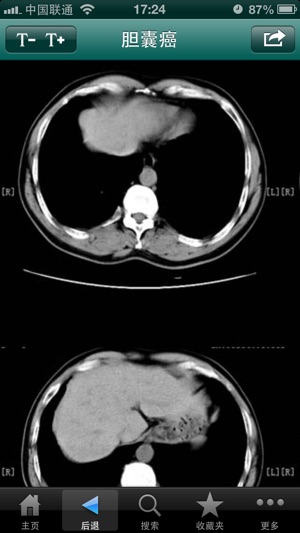

‎全科医生(专业版)收藏夹离线功能,让您在没有网络的环境下,也可随时查看。 临床决策需要信息、知识和经验三方面的支持,而知识的价值取决于它的相关性、正确性和易获得性。MediX®的使命就是以最便捷的方式(at point of care)提供与临床决策高度相关且准确可靠的知识。 MediX®是利用现代计算机及网络通信技术专门面向一线医务工作者开发的基于知识管理的临床问题求解系统,由结构化的临床医学知识库及软件化的决策工具所组成。 临床益处: 1. 明显提高工作效率 美国一项调查,90%以上被访问的医务人员承认电子化的临床信息和决策支持工具可以帮助他们迅速找到所需的资讯;三分之一的医生认…